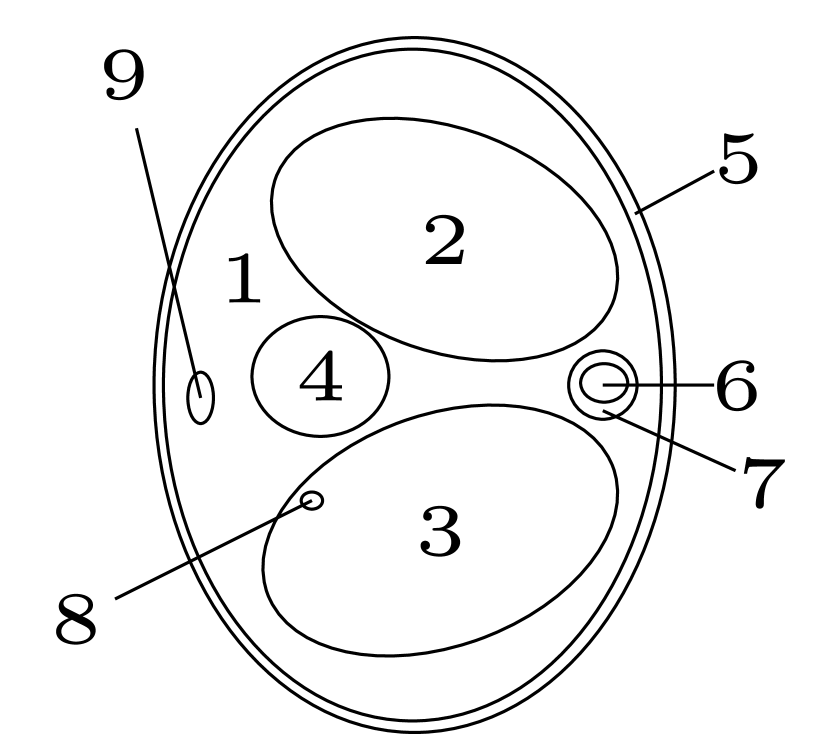

| ellipse number | 1 | 2, 3 | 4 | 5 | 6 | 7, 9 | 8 |

|---|---|---|---|---|---|---|---|

| 0.907 | 0.380 | 1.190 | 1.300 | 1.116 | 1.784 | 1.077 |

We assume to measure a total of photons and compute synthetic data from eq. 11 for a phantom electron density modeling a transversal slice of a human thorax. The phantom (see fig. 2(b)) consists of characteristic functions of ellipses of different sizes and opacities and is a modified version of an earlier phantom which was used in [12]. It is 28.4 cm resp. 21.3 cm wide at its largest and smallest diameters and its gray values are chosen as electron densities of materials typical in a human thorax [15, 3, 30].